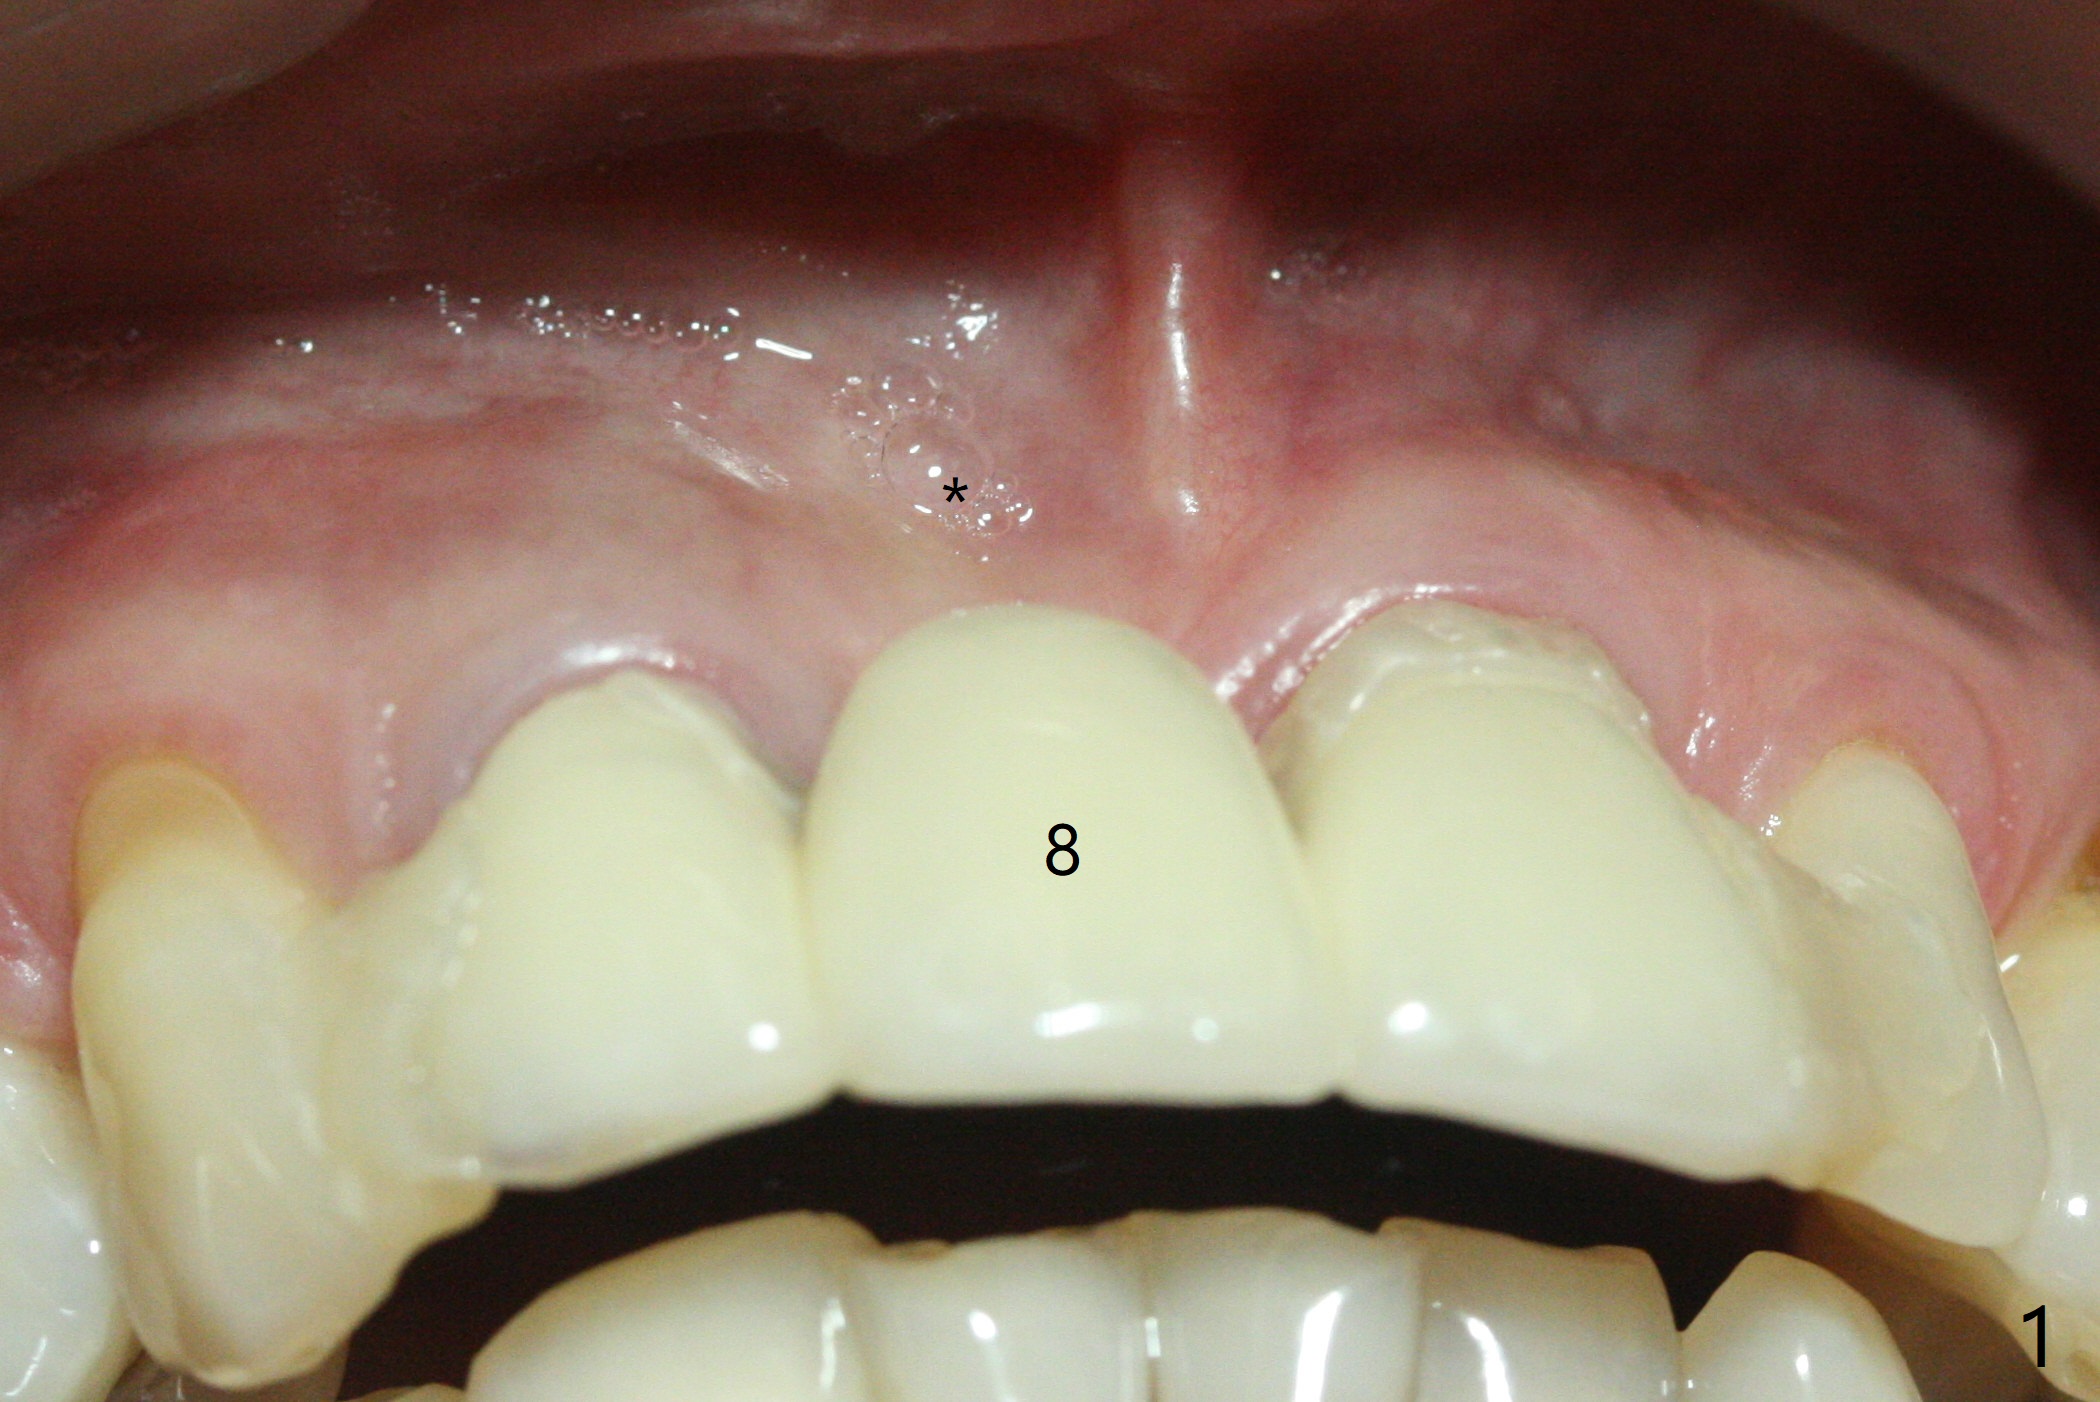

Since the pontic (Fig.1 #8) of the existing failed FPD has severe buccal concavity (*), socket shield is performed when #7 and 9 are extracted (Fig.2,3 *). Angled abutments are placed when 3.5x13 mm implants are inserted with guide. An immediate provisional FPD is fabricated. Acrylic is added to the pontic of the temporary FPD (Fig.4 arrow) to form a concave pontic gingiva (blanch)16 days postop. The patient returns 3.5 m postop with concern over temp being bulky and turning yellow. With Cetacaine and 1-0 cord, labial reducion is done for 7,9 abutments as well as 7 incisal reduction. The provisional is relined to increase 7 8 crown length. Next visit we will continue modification of temporary. Photos will be taken before and after modification (buccal and incisal views). The patient complains of occasional pain at #7. Check whether the socket shield at #7 is a culprit. In fact the implant at #7 is normal. Manipulation of the provisional does not help cosmetics much. A permanent restoration is delivered 5.5 months postop (Fig.7-9).